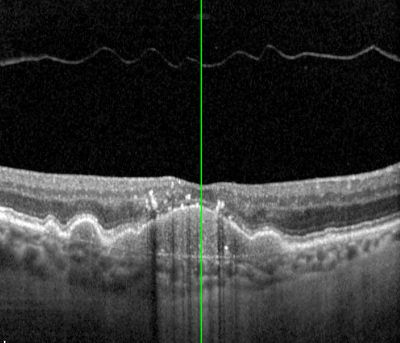

OCT